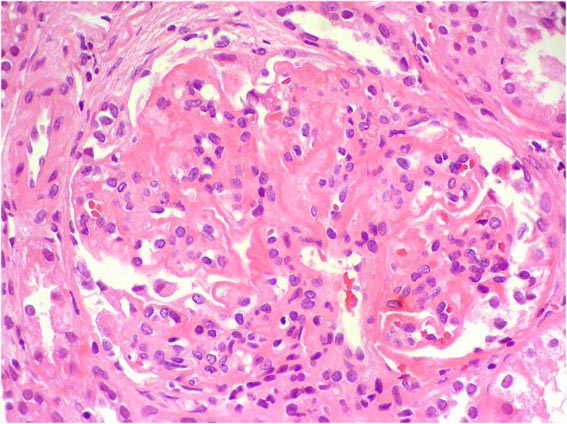

Figura 2.

H&E, X400.